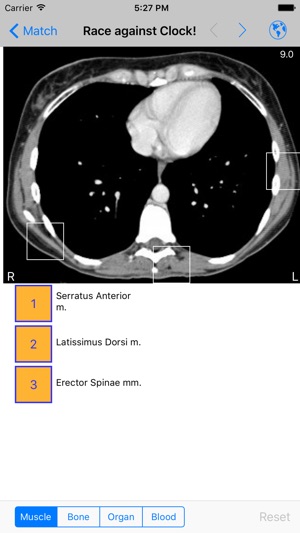

‎WINNER: NLM "Show Off Your Apps" iAnatomy: A simple, portable anatomy atlas of the face, neck, chest, abdomen, and pelvis. -75 images with 60 actual CT scans of the chest, abdomen, and pelvis -Cadaveric images of the face and neck -Separate male and female pelvis -Over 1300 anatomy identifying labe…